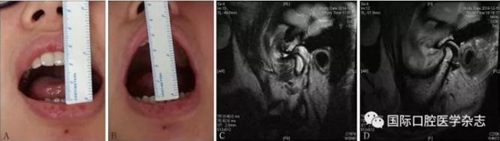

A:術(shù)前開口度;B:術(shù)后開口度;C:術(shù)前影像學(xué)檢查片;D:術(shù)后影像學(xué)檢查片。

圖 18 關(guān)節(jié)盤復(fù)位錨固術(shù)前后對(duì)比